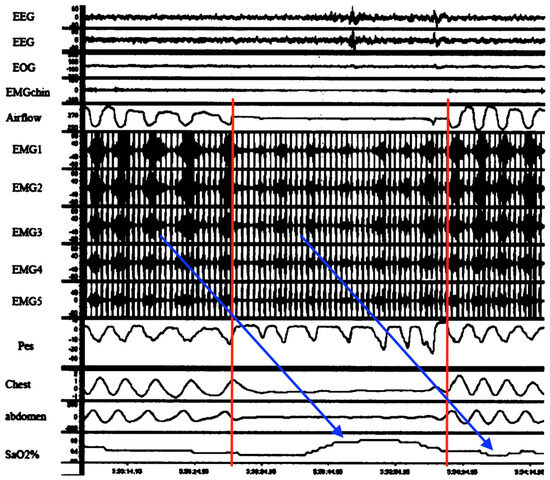

Figure 9 is very important because it temporally connects abnormal diaphragmatic electrical activity on intra-esophageal D-EMG in an adult apnea with a complete lack of ventilatory movements. It was neither a classic central, obstructive nor even mixed apnea. Although cause and effect cannot be ascertained, there was significant attenuation of D-EMG amplitude (and frequency) during the episode. Combined with the lack of respiratory movements, this is consistent with diaphragm inactivation due to spasm (electromechanical dissociation). Respirations resumed but only with higher intensity electrical bursts (perhaps from increased neural drive and higher diaphragm work to overcome post-obstruction airway resistance). Also, although truncated, D-EMG and oxygen saturations exhibited periodicity, suggestive of respiratory load cycling with RAM. Lastly, this evidence suggests that D-EMG activity reflects not just neural drive, but rather a composite influenced by diaphragm electromechanical output.